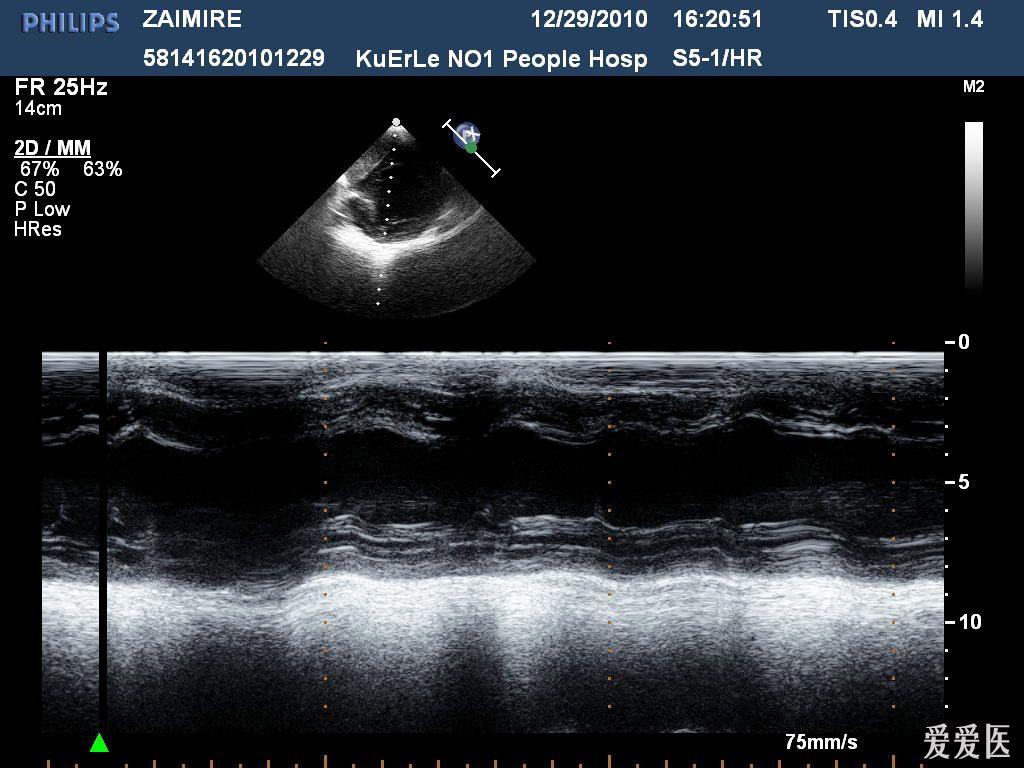

图2‐1‐194 组织多普勒成像正常人二尖瓣环水平组织频谱多普勒,em>am